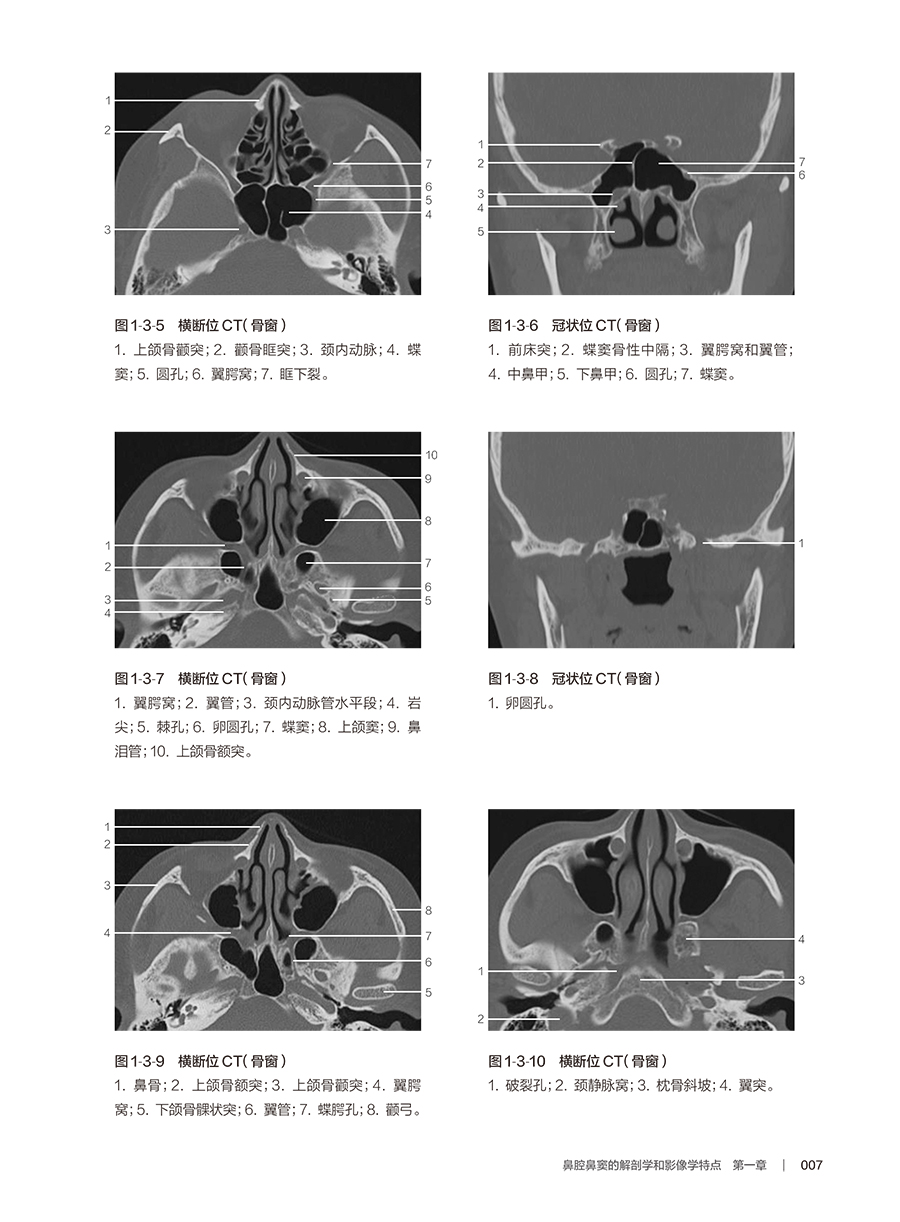

2.详细阐述鼻腔鼻窦的解剖学特点及鼻腔鼻窦恶性肿瘤病理学特点,并结合近年对恶性肿瘤神经侵犯的临床重要意义的认识,详细阐述鼻腔鼻窦的神经网络分布及其在肿瘤侵袭发展中的作用和特点。